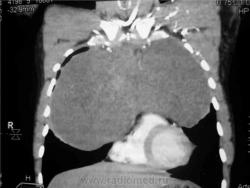

КТ август 2009.

КТ контроль октябрь 2009

Интенсивное, однородное затемнение в средних отделах справа, слева норма - мною был заподозрен м/долевой плеврит, пациент был направлен в областной центр торакальной хирургии. Затем онкодиспансер, затем институт рака в Киеве. Результат гистологии тератобластома средостения. 2 курса химиотерапии контрольное КТ в октябре - отрицательная динамика.